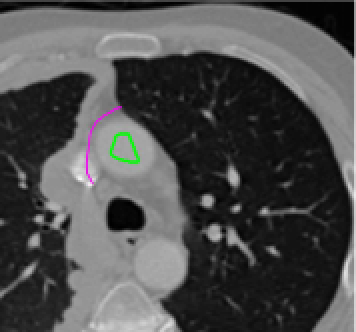

Problem 3: Blurred edges.

If there are blurred edges between objects in an image, the geodesic distance will not increase significantly at this edge. Therefore the final segmentation result is liable to include unwanted objects. We look to address this problem through the use of anti-markers. These are markers which indicate objects that we do not want to segment, i.e. the opposite of marker points, we denote the set of anti-marker points by 𝒜𝒜\mathcal{AM}.

Refer to caption

Figure 6: (Left to right:) original image, \mathcal{M} (green) and 𝒜𝒜\mathcal{AM} (pink), segmentation result just using marker set, 𝒟AM(x,y)subscript𝒟𝐴𝑀𝑥𝑦\mathcal{D}_{AM}(x,y) using anti-markers, segmentation result using anti-markers. For these μ=1,λ1=λ2=5,θ=25formulae-sequenceformulae-sequence𝜇1subscript𝜆1subscript𝜆25𝜃25\mu=1,\lambda_{1}=\lambda_{2}=5,\theta=25.

We propose to use a geodesic distance map from the set 𝒜𝒜\mathcal{AM} denoted by 𝒟AM(x,y)subscript𝒟𝐴𝑀𝑥𝑦\mathcal{D}_{AM}(x,y) which penalises pixels near to the set 𝒜𝒜\mathcal{AM} and doesn’t add any penalty to those far away. We could naïvely choose 𝒟AM(x,y)=1𝒟~GAM(x,y)subscript𝒟𝐴𝑀𝑥𝑦1subscript~𝒟𝐺𝐴𝑀𝑥𝑦\mathcal{D}_{AM}(x,y)=1-\tilde{\mathcal{D}}_{GAM}(x,y) where 𝒟~GAM(x,y)subscript~𝒟𝐺𝐴𝑀𝑥𝑦\tilde{\mathcal{D}}_{GAM}(x,y) is the normalised geodesic distance from 𝒜𝒜\mathcal{AM}. However this puts a large penalty on those pixels inside the object we actually want to segment (as 𝒟~GAM(x,y)subscript~𝒟𝐺𝐴𝑀𝑥𝑦\tilde{\mathcal{D}}_{GAM}(x,y) to those pixels is small). To avoid this problem, we propose the following anti-marker distance term

𝒟AM(x,y)=exp(α~𝒟~GAM(x,y))exp(α~)1exp(α~)subscript𝒟𝐴𝑀𝑥𝑦~𝛼subscript~𝒟𝐺𝐴𝑀𝑥𝑦~𝛼1~𝛼\mathcal{D}_{AM}(x,y)=\frac{\exp\left(-\tilde{\alpha}\tilde{\mathcal{D}}_{GAM}(x,y)\right)-\exp\left(-\tilde{\alpha}\right)}{1-\exp\left(-\tilde{\alpha}\right)}

where α~~𝛼\tilde{\alpha} is a tuning parameter. We choose α~=200~𝛼200\tilde{\alpha}=200 throughout. This distance term ensures rapid decay of the penalty away from the set 𝒜𝒜\mathcal{AM} but still enforces high penalty around the anti-marker set itself. See Figure 6 where a segmentation result with and without anti-markers is shown. As 𝒟AM(x,y)subscript𝒟𝐴𝑀𝑥𝑦\mathcal{D}_{AM}(x,y) decays rapidly from 𝒜𝒜\mathcal{AM}, we do require that the anti-marker set be close to the blurred edge and away from the object we desire to segment.